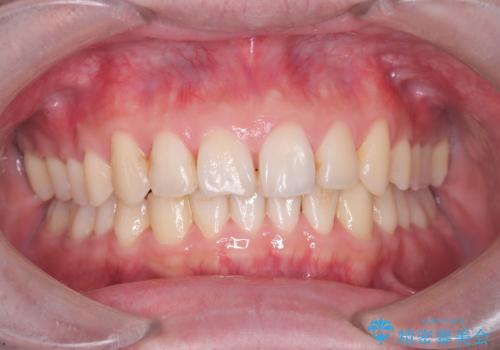

- 前歯の凸凹と顎の偏位を主訴に来院されました。

下顎の偏位を認めましたが、外科矯正を希望されなかったためできる範囲で顎の偏位を治すことができるよう治療を行なっております。

治療開始前に、下顎位の評価をおこなうことで、完成度の高い治療を行うことができました。